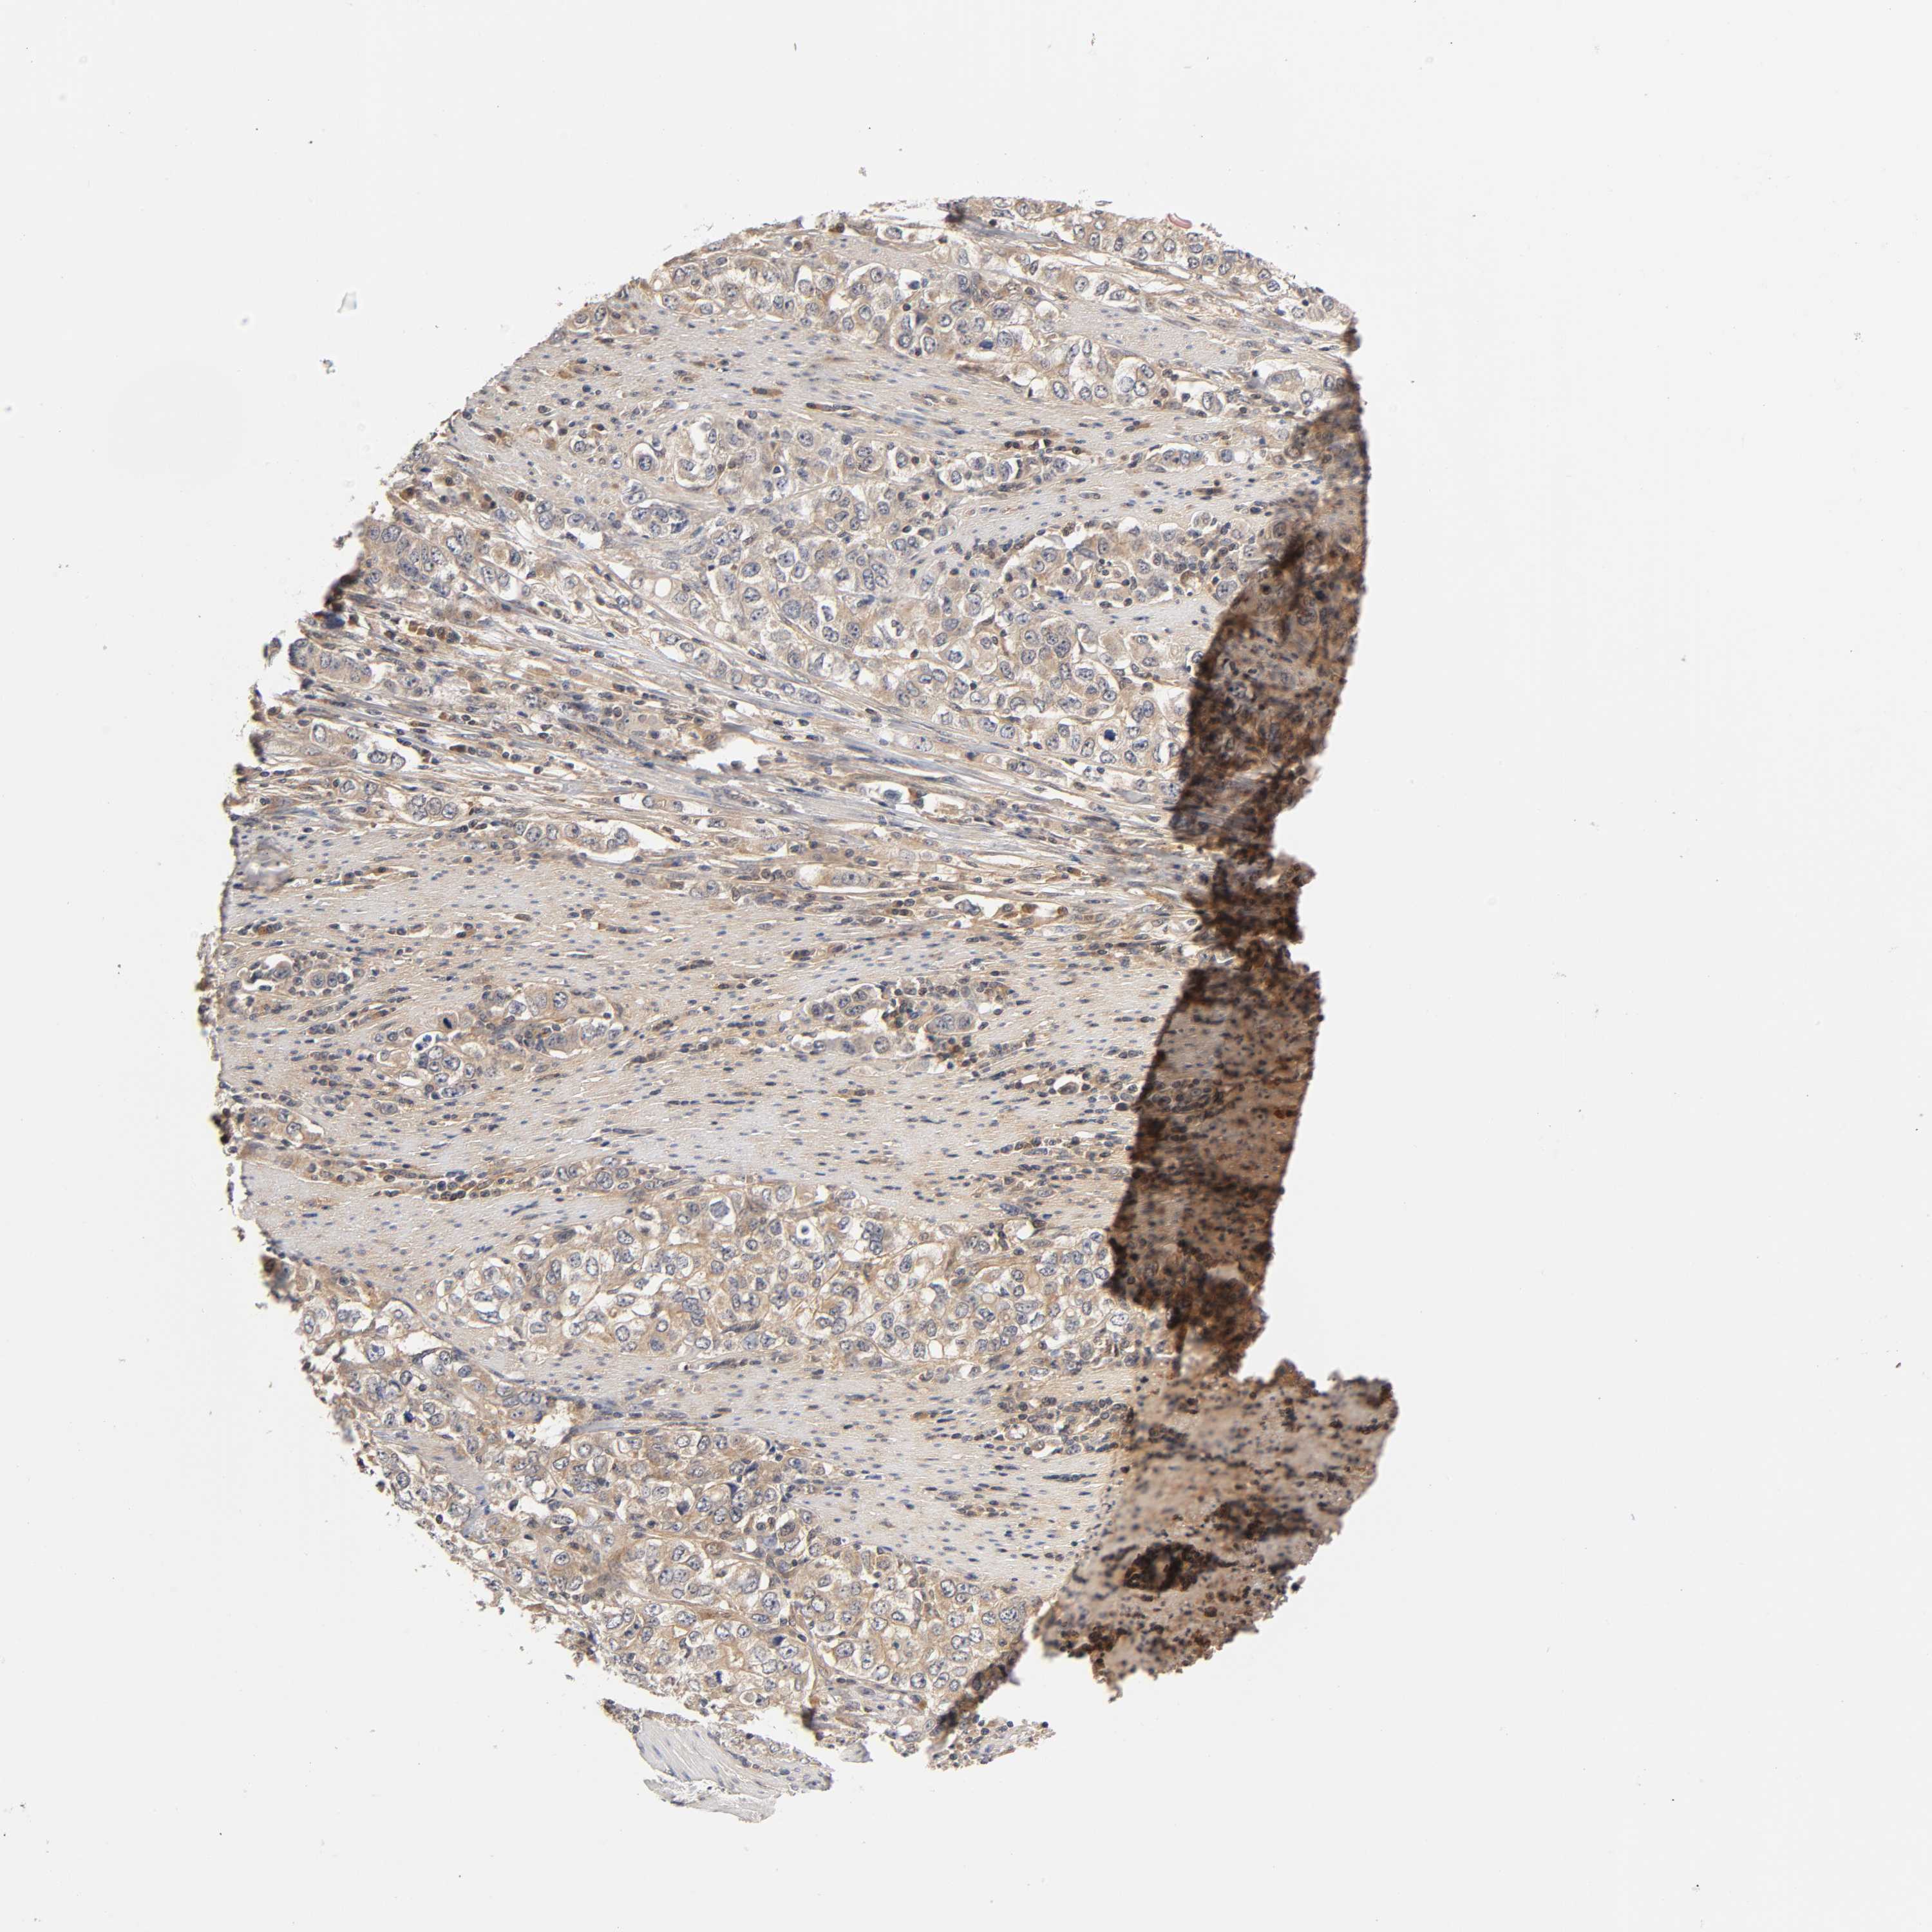

STOMACH CANCER - Protein expressioni

A mouse-over function shows sample information and annotation data. Click on an image to view it in a full screen mode. Samples can be filtered based on level of antibody staining by selecting one or several of the following categories: high, medium, low and not detected. The assay and annotation is described here.

Antibody stainingi

Antibody staining in the annotated cell types in the current human tissue is reported as not detected, low, medium, or high, based on conventional immunohistochemistry profiling in selected tissues. This score is based on the combination of the staining intensity and fraction of stained cells.

Each image is clickable and will lead to virtual microscopy that enables deeper exploration of all samples and also displays staining intensity scores, fraction scores and subcellular localization as well as patient and tissue information for each sample.

Antibody HPA004729

Antibody HPA012873

Staining

High

Medium

Low

Not detected

Intensity

Strong

Moderate

Weak

Negative

Quantity

>75%

75%-25%

<25%

None

Location

Nuclear

Cytoplasmic/membranous

Cytoplasmic/membranous,nuclear

Adenocarcinoma, NOS

Adenocarcinoma, High grade